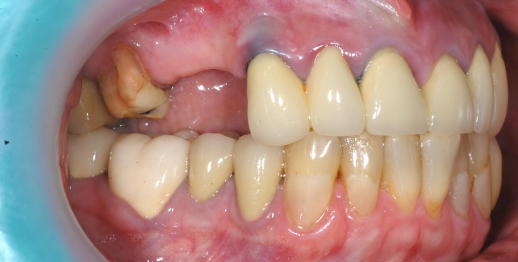

Upper jaw dental implants and bone graft

55 y.o, Russia

Operating dentist: Roh Hyun Ki